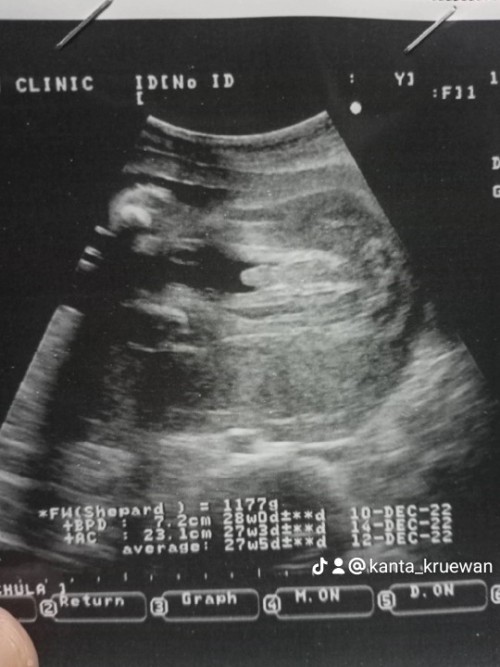

หมอบอกชาย ทำไมเล็กจัง